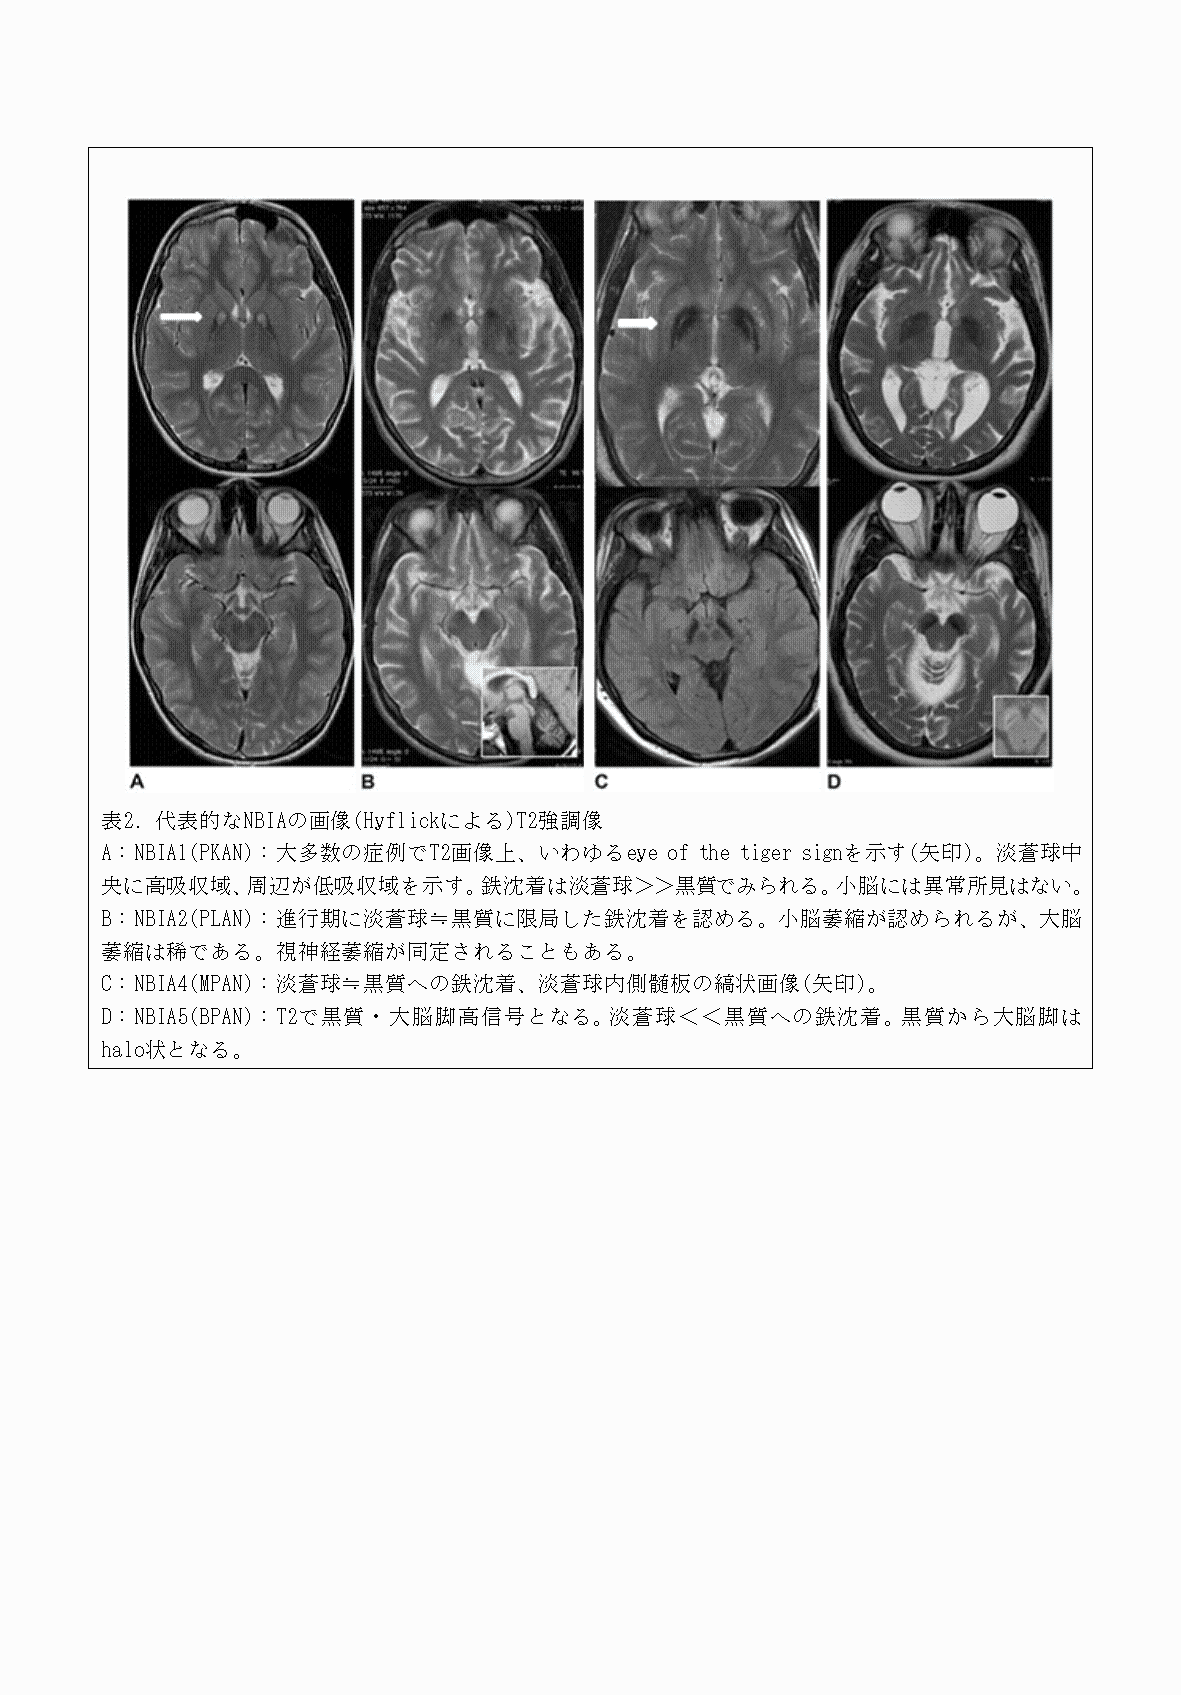

2FH00000070628-4.png